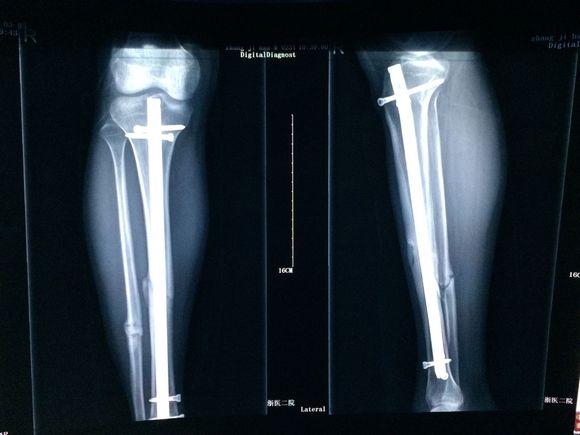

骨折愈合图片对比x光,骨折愈合图片x光

术后x线片提示:原骨折处愈合良好,钢板内固定完全取出.

骨折愈合图片x光

小腿骨折愈合图片